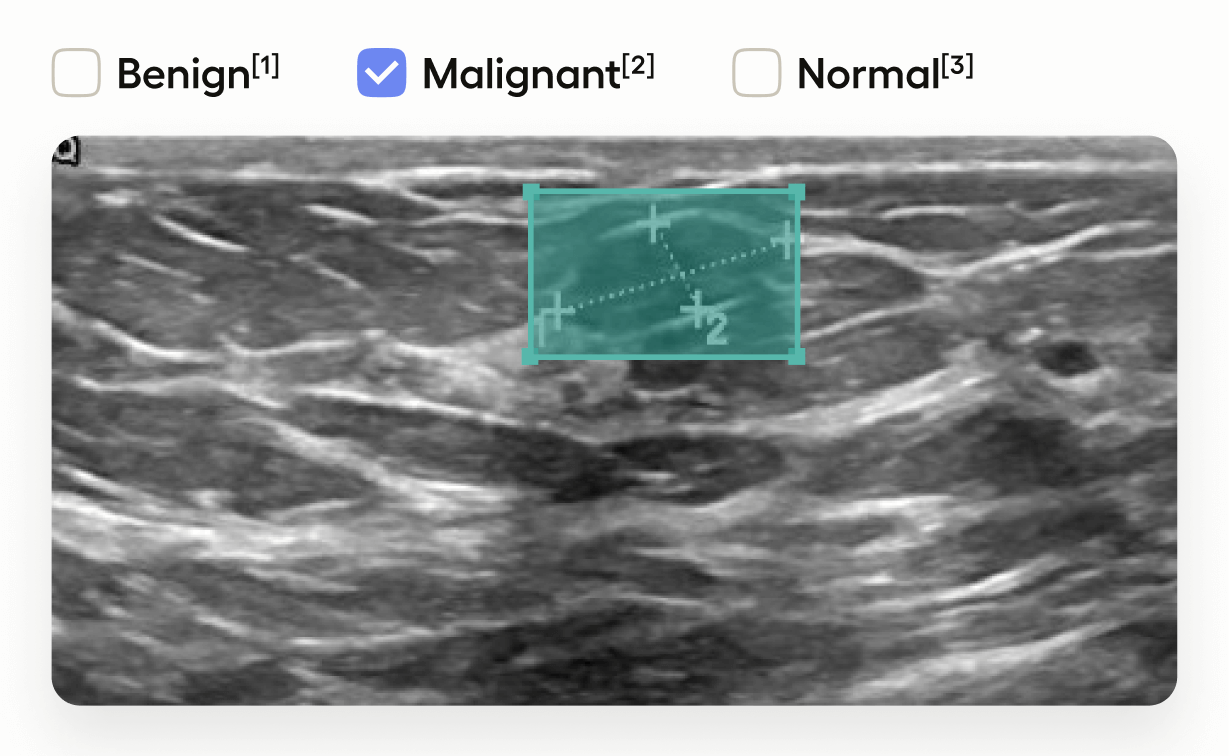

Medical Image Classification with Bounding Boxes

This template interface allows annotators to:

• Draw bounding boxes around areas identified as tumors in the image using the “Tumor” label.

• Classify the entire image by selecting one of “Benign”, “Malignant”, or “Normal”.

This setup is useful in medical imaging tasks where you need to localize tumors and also provide an overall assessment of the image.